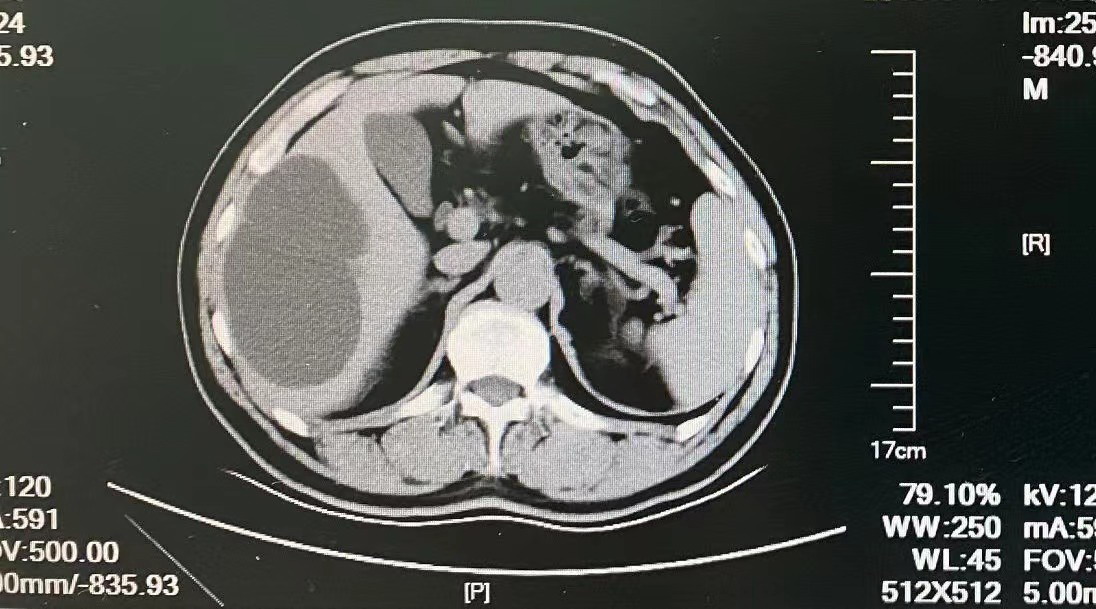

我们首先为患者进行了详细的体格检查,患者腹部平坦、柔软,轻轻按压时、轻放时没有疼痛,肋骨下缘没有触及肝脏、脾脏,其它心脏、肺部、腹部均无明显异常。因此,初步考虑为“肝囊肿”,性质有待进一步确定。为了进一步了解肝脏情况,我们为患者进行上腹部增强CT。相对于彩超,增强CT可以更好鉴别肝囊肿、肝脓肿、肝癌等疾病。通过CT,我们发现患者肝内多发低密度影、不强化,最大者在肝下角,11.3*7.1厘米,这是肝囊肿的表现。从CT结果中,还可以排除患者是寄生虫性(肝棘球蚴病)的可能。